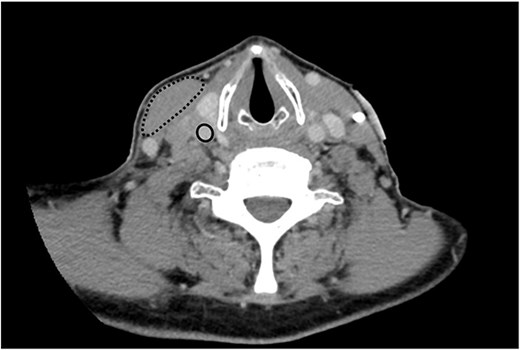

Computed tomography (CT) scan of his neck and chest was performed in anticipation of permanent pacemaker insertion, and demonstrated a mass at the level of the carotid artery measuring 3.6 cm in its maximal dimension causing occlusion of the right internal jugular vein and extrinsic compression on the right carotid artery (Fig. 2). During attempted ultrasound-guided lymph node biopsy, the patient developed transient hypotension, bradycardia, and altered consciousness requiring resuscitation. In the following days, the patient had recurrent episodes of symptomatic bradycardia and hypotension despite transvenous pacing, including an episode of pulseless electrical activity and bradycardic arrest requiring 3 minutes of cardiopulmonary resuscitation before return of spontaneous circulation.

Axial plane image of contrast-enhanced CT scan demonstrating right-sided neck mass displacing the right sternocleidomastoid muscle (dashed line), occluding the right internal jugular vein (not seen) and compressing the right carotid artery (solid line) .